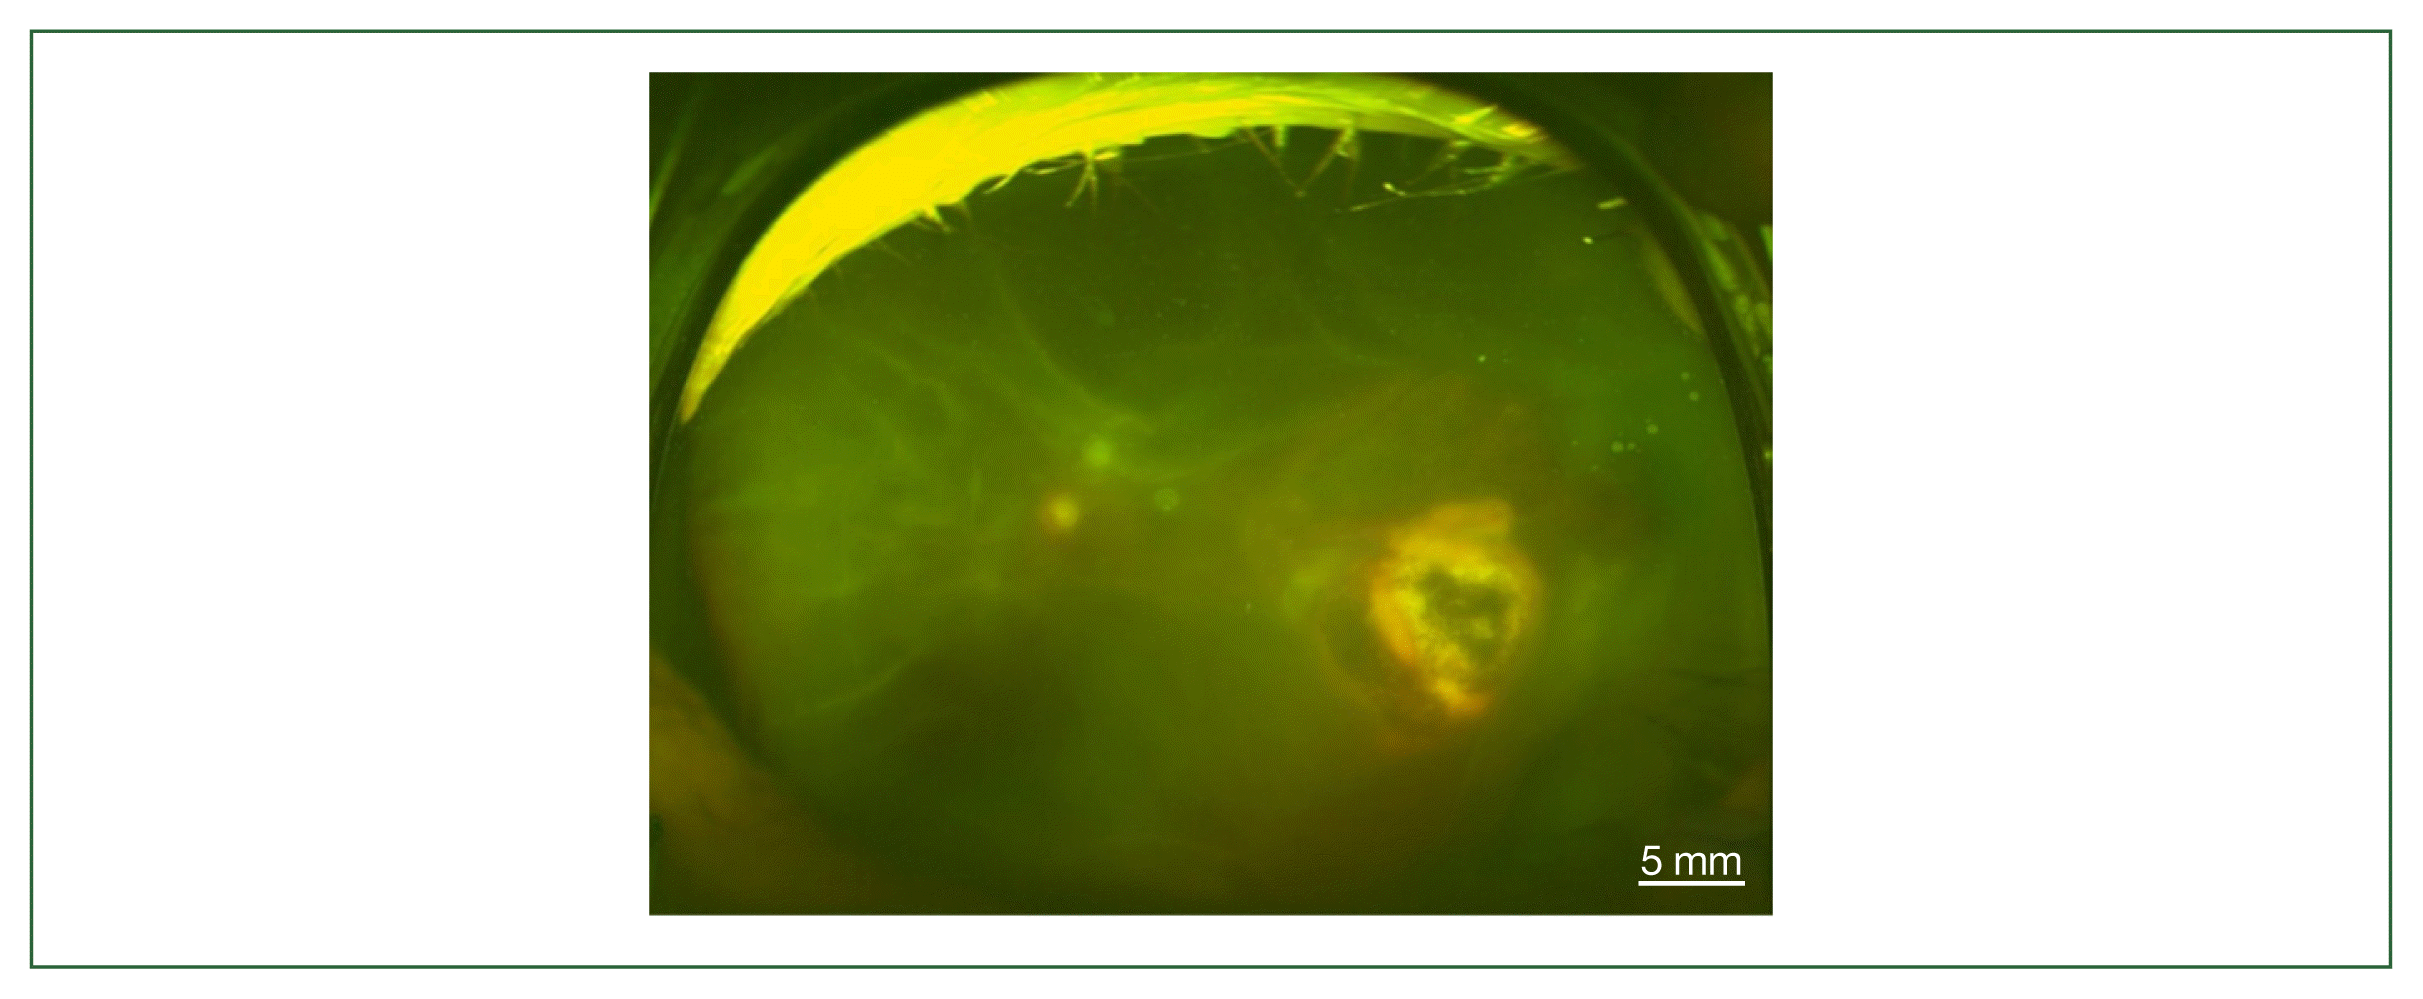

The 4 patients presented persistent unilateral visual disturbance 2–3 months before assessment. The ocular examination revealed that all study patients also exhibited unilateral panuveitis. Two patients (cases 1 and 2) did not show signs of chorioretinal scars, while the other 2 patients (cases 3 and 4) had preexisting scars on the retina and choroid. All of them showed an initial decimal visual acuity between 0.1 and 0.5. The ophthalmic analysis also revealed active retinochoroiditis in the 4 patients (Fig. 1) and papillitis and periphlebitis in cases 1 and 4, which were more evident by fundus fluorescein angiography (Fig. 2). All study patients also exhibited vitritis and anterior uveitis. Three patients (cases 1, 3, and 4) who underwent vitrectomy for diagnostic and therapeutic reasons had negative cytology for lymphoma cells. The remaining patient (case 3) had re-vitrectomy combined with scleral encircling for total retinal detachments developed later (Fig. 3). Only 1 patient (case 1), who was previously diagnosed with acute retinal necrosis (ARN) in a local ophthalmology clinic, received a systemic steroid treatment (60 mg per day) for posterior uveitis before visiting the Eye Center at the Seoul St. Mary Hospital, Catholic University. None had received any medication (including antibiotics) before the examination.

Fig. 1

Fundus photographs of vitritis (headlight in the fog) with active lesions seen as whitish foci of retinochoroiditis which is marked by white dotted circles; (A) left eye of case 1, (B) left eye of case 2, (C) left eye of case 3, (D) right eye of case 4, and (E) unaffected left eye of case 4.

Fig. 3

Fundus photography of total retinal detachment associated with active ocular toxoplasmosis (left eye of case 3).